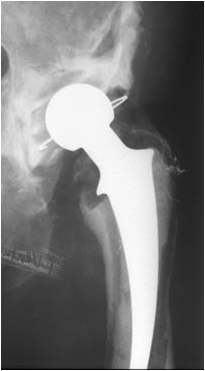

mplex reconstruction in a case where the socket(acetabulum) has been totally damaged after years of usage of 1st Hip replacement.